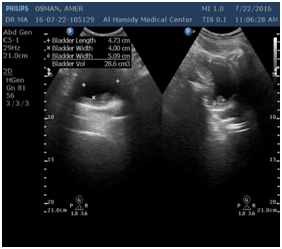

The first and most clinical and cost effective diagnostic tool are urine analysis and ultrasound (Figure 5). CT scan might be used later for further evaluation (Figure 5).

Figure 5 Urothelial cancer in different modalities.